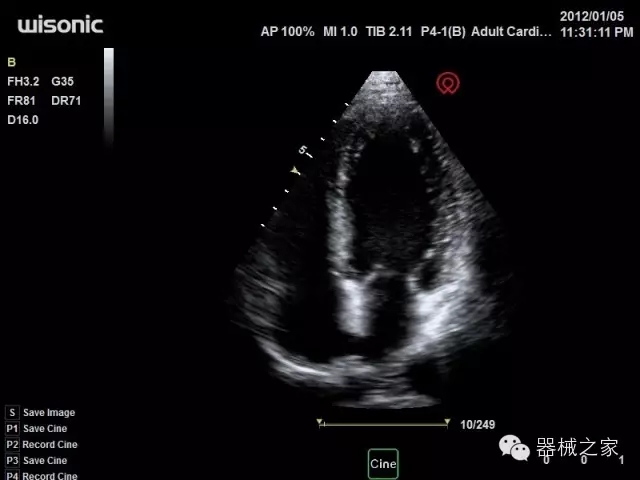

臨床圖片賞析

產(chǎn)品特點

·全球目前唯一一款配備主機雙探頭接口,整機重量(含電池)在5公斤以內(nèi)的便攜式彩超;

·一款互聯(lián)網(wǎng)彩超,只要有手機信號的地方就可以非常方便地實現(xiàn)遠程會診和病案調??;

·鎂鋁合金外殼,堅固可靠耐用;